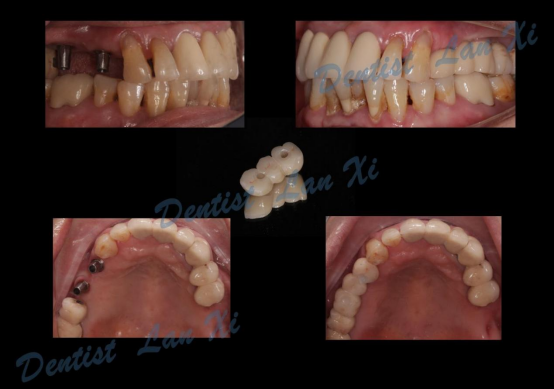

第六步:最终修复

一、以终为始 更精准

在数字化种植导板下,通过CBCT、口扫等途径获取口腔三维信息内容。使患者在种植之前就可以了解到种植方案的相关细节,清晰地看到牙齿修复之后的模拟展示图,提前预知种植术后的效果。

除此之外,数字化种植导板还可实现以修复为导向的种植方案设计,使得术后即刻修复成为可能,提高了修复后美学及功能效果的可预见性。